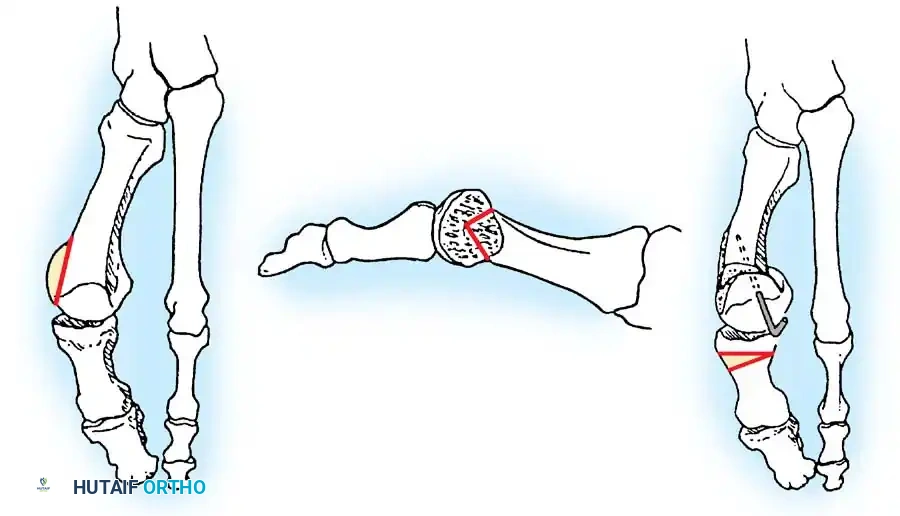

Two other anatomical variants involving the articular surface of the fi rst metatarsophalangeal joint can lead to hallux valgus. In the fi rst variant, the articular surface of the metatarsal head is offset, resembling a scoop of ice cream sitting at an angle on a cone (Fig. 78-6). This has been described as the distal metatarsal articular angle (see Fig. 78-8). In the second, the articular angle of the base of the proximal phalanx in relation to its longitudinal axis is offset. This has been described as the phalangeal articular angle. Although the normal range of these angles is generally considered to be 7 to 10 degrees for the phalangeal articular angle and 10 to 15 degrees for the distal metatarsal articular angle, exact measurements are diffi cult to reproduce because of the variability of radiographic and measurement techniques. Increasing evidence indicates, however, that the failure to correct these two deformities, especially the distal metatarsal articular angle, can cause unsatisfactory results after surgery in some patients. Forceful straightening of the hallux should be avoided if it sacrifi ces tarsalgia. The entire forefoot must be evaluated for these multiple components of hallux valgus before surgical planning is complete and recommendations can be made to the patient. The controversy continues over which deformity is the essential lesion in hallux valgus: metatarsus primus varus or lateral deviation of the great toe. Each is incriminated as the cause of the other. The strongest data probably support lateral deviation of the great toe as the primary deformity in most patients, followed by medial angulation of the fi rst metatarsal, but metatarsus primus varus may be the principal cause in adolescents. Further controversy surrounds the role of footwear as the prime offender in the development of hallux valgus. Most orthopaedic surgeons have seen unilateral hallux valgus when both feet are clinically and radiographically the same structurally except that one foot has a bunion deformity and the other foot is normal. Evidence supports that hallux valgus may be familial, especially when it occurs in adolescents. Although no study of shod and unshod societies has implicated inappropriate footwear as the sole cause of hallux valgus, after genetic factors, binding, unphysiologically designed footwear probably is the major cause in modern societies. Hypermobility of the fi rst ray also has been suggested as a causative factor in the development of hallux valgus and fi rst metatarsal varus, but this is controversial. Coughlin and Shurnas, Myerson and Badekas, King and Toolan, and Faber et al. offer excellent discussions of this problematic area. Finally, certain anatomical and structural abnormalities almost certainly play a causative role in hallux valgus. Pronated fl atfeet, abnormal insertion of the posterior tibial tendon, increased obliquity of the fi rst metatarsomedialcuneiform joint, an abnormally long fi rst ray, incongruous articular surfaces of the fi rst metatarsophalangeal joint, and excessive valgus tilt of the articular surface of the fi rst metatarsal head and proximal phalangeal articular surface may contribute singly or in combination to the deformity and infl uence the recommended treatment. Hypertrophy of the medial eminence has been described as a component of hallux valgus deformity since the earliest reports; however, more recent investigations, including those of Thordarson and Krewer, have found that bony proliferation is not a component of the pathoanatomy of hallux valgus and that the prominence of the medial eminence results from the combination of metatarsus primus varus and medial deviation that uncovers the articular surface. Thordarson and Krewer compared radiographs of 50 feet in patients who had surgery for hallux valgus deformity with radiographs of 50 feet from a control group without hallux valgus deformity and found little difference in the average width of the medial eminence (4.4 mm and 4.1 mm). With more than 130 operations recommended for the treatment of hallux valgus, it is practical to describe only

Fig. 78-6 A, Note valgus orientation of articular surface of fi rst metatarsal head. B, After proximal metatarsal osteotomy on right foot. Sesamoid sling remains dislocated, articular surface of metatarsal head maintains valgus posture, and joint is congruous in valgus. Double osteotomy of fi rst metatarsal (proximally for varus correction and distally for valgus correction of articular surface) and soft-tissue realignment are necessary. Alternatively, arthrodesis of fi rst metatarsophalangeal joint or distal metatarsal osteotomy (chevron) can be performed. Without anatomical reduction of sesamoid sling apparatus, distal metatarsal osteotomy would fail.